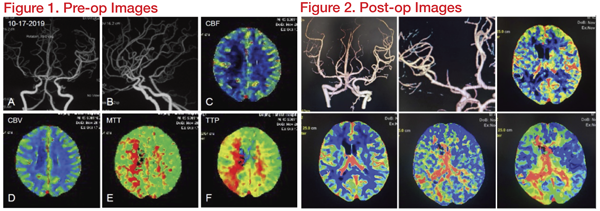

A 45-year-old man presented with chronic aphasia and left hemiparesis. His right middle cerebral artery (R-MCA) showed 85 percent stenosis. He was treated with medical therapy, but it was not effective. Hence, he was referred for angioplasty and stenting.

In this case, the middle and distal segments of the middle cerebral artery were severely narrowed, and the stenosis was adjacent to the bifurcation, but did not spread to the upper and lower trunk openings. The undersized balloon (Gateway1.5*15mm) was chosen, following the open cell stent with accurate deployment. A 2.5*15mm Wingspan stent was delivered to the lesions. The guide wire landing area was selected to be the lower trunk, which is smooth and has a larger diameter. This reduced the damage of the branching vessels due to the expansion of the bifurcation. After the stent was implanted, the lumen became thinner at the proximal end of the stent. We consider vasospasm to be the cause. After intravenous injection of nimodipine, the angiogram showed quick relief. In addition, the lenticulostriate artery is centred on the medial side, and the opening has a certain anatomical distance from the proximal end of the stenosis. The risk of perforating complications after intravascular interventional therapy is relatively low.